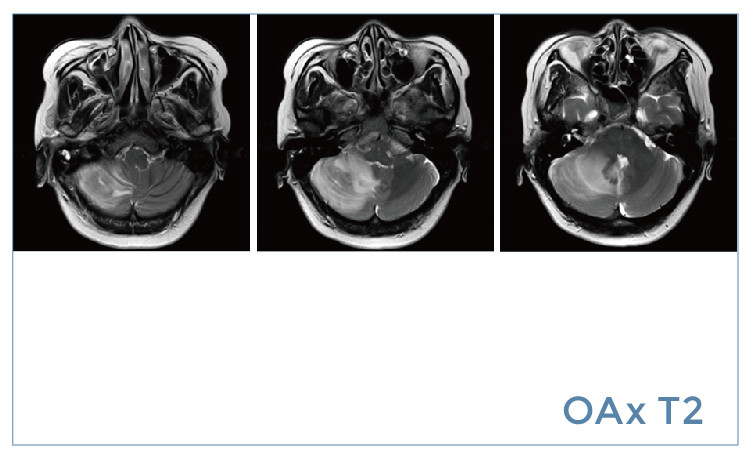

【朗润影像档案】20190802磁共振影像病例结果讨论